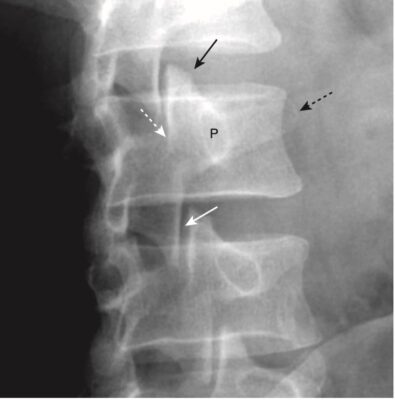

- Trên phim chụp X quang cột sống thắt lưng thông thường ở tư thế chếch, các cấu trúc giải phẫu thường chồng lên nhau, tạo nên một hình bóng giống như phần trước của loài chó sục Scotland, dấu hiệu chú chó Scottie (Scottie dog) nổi tiếng (Hình 3).